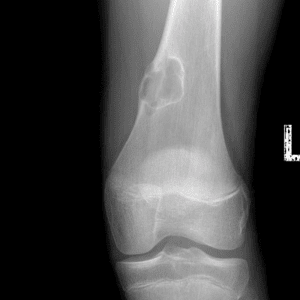

Pediatric Radiographs